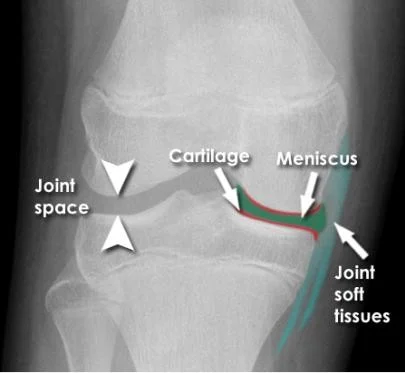

Reading Joints

- Position

- Relations

- Alignment

- Joint âSpaceâ

- Joint line

- Subchondral bone

Joint Position and Relations

Joint Anatomy

- The annotations include:

- Joint space

- Cartilage

- Meniscus

- Joint soft tissues

Bone and Joint Alignment

Joint Space

- **Joint narrowing**

- **Osteophytes**